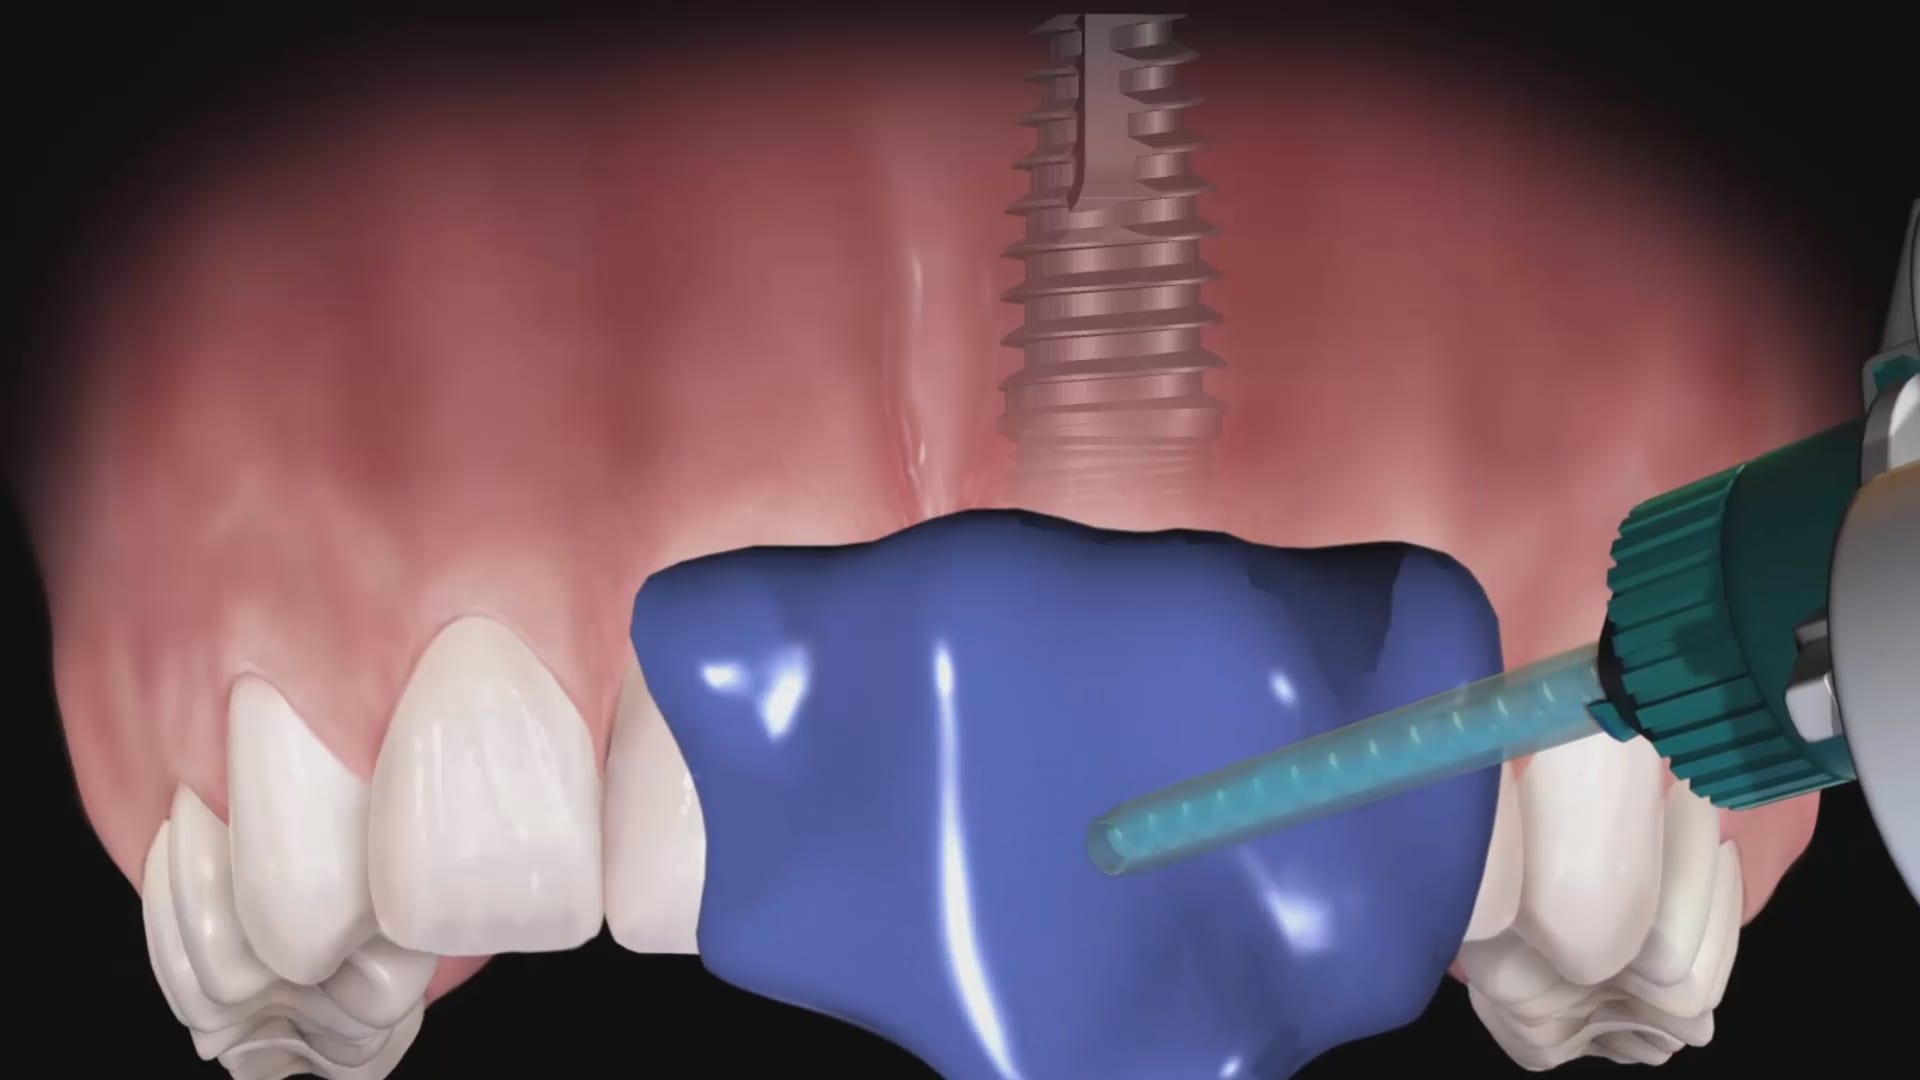

Live Intra-Oral Scan Verification Jigs for Full Arch Scans and Global Accuracy

October 25, 2019This is a detailed video demonstration that shows you how to capture full arch scans for multi unit implant cases in edentulous jaws and, more importantly, how to assess its […]